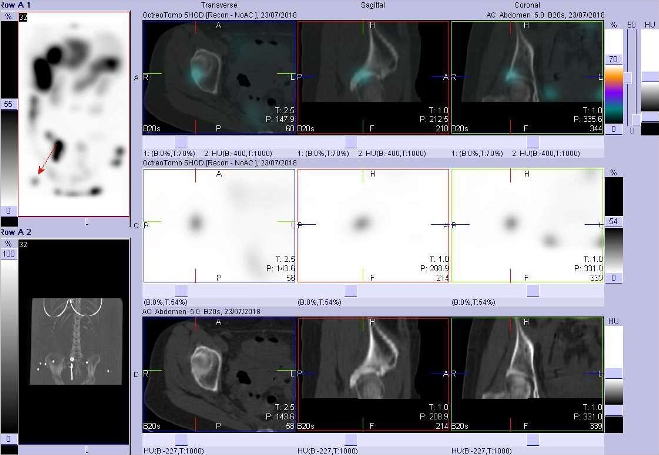

/ Obr. č. 11: Fúze SPECT/CT 5 hod. po aplikaci OctreoScanu. Zaměřeno na ložisko v pravé kyčli.

/